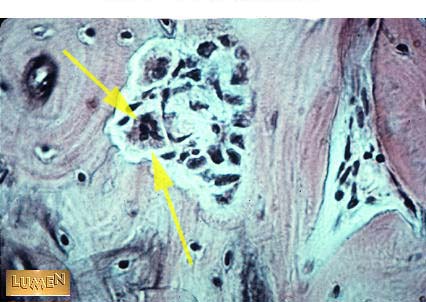

What cell is this?

Osteoclast